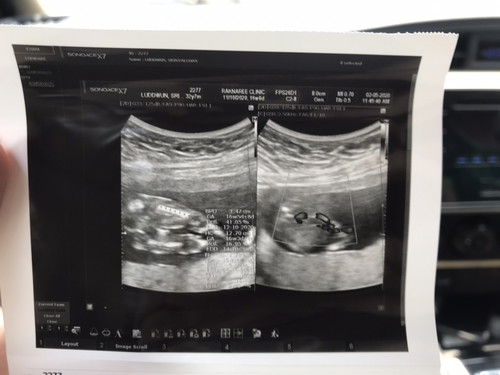

ซาวด์ 16 week ท่านอนคว่ำ ชัวร์หรือมั่วกันแน่

เพิ่งไปซาวด์ ดูความสมบูรณ์มาวันนี้ค่ะ น้องสมบูรณ์แข็งแรงดี คุณหมอบอกน้องผู้ชาย แต่ท่าที่น้องนอนคือนอนคว่ำนะคะ อยากทราบว่ามีแม่ๆคนไหนมีประสบการณ์ซาวด์ท่านอนคว่ำ บ้างคะ อยากรู้ว่าผลชัวร์หรือป่าว เพราะจริงๆที่บ้านลุ้นอยากได้สาวน้อย มากกว่า หนุ่มน้อยค่ะ

บ้านตอนซาวด์16W นอนคว่ำเหมือนกันจ้า หมอบอกน่าจะผู้ชายจ้า รอบคอนเฟริมรอบหน้าจ้า แม่แอบลุ้นไห้หมอดูผิด เพราะอยากได้ผู้หญิง😂😂